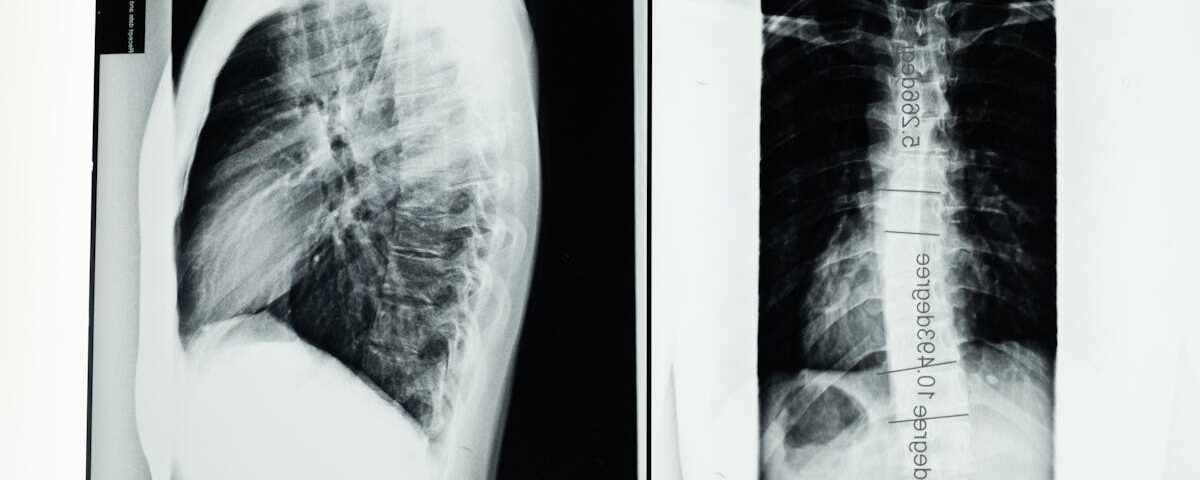

Est-il nécessaire d’effectuer des examens avant de commencer la décompression neurovertébrale?

Oui, des examens comme une IRM ou des radiographies sont souvent recommandés pour évaluer l’état de la colonne.